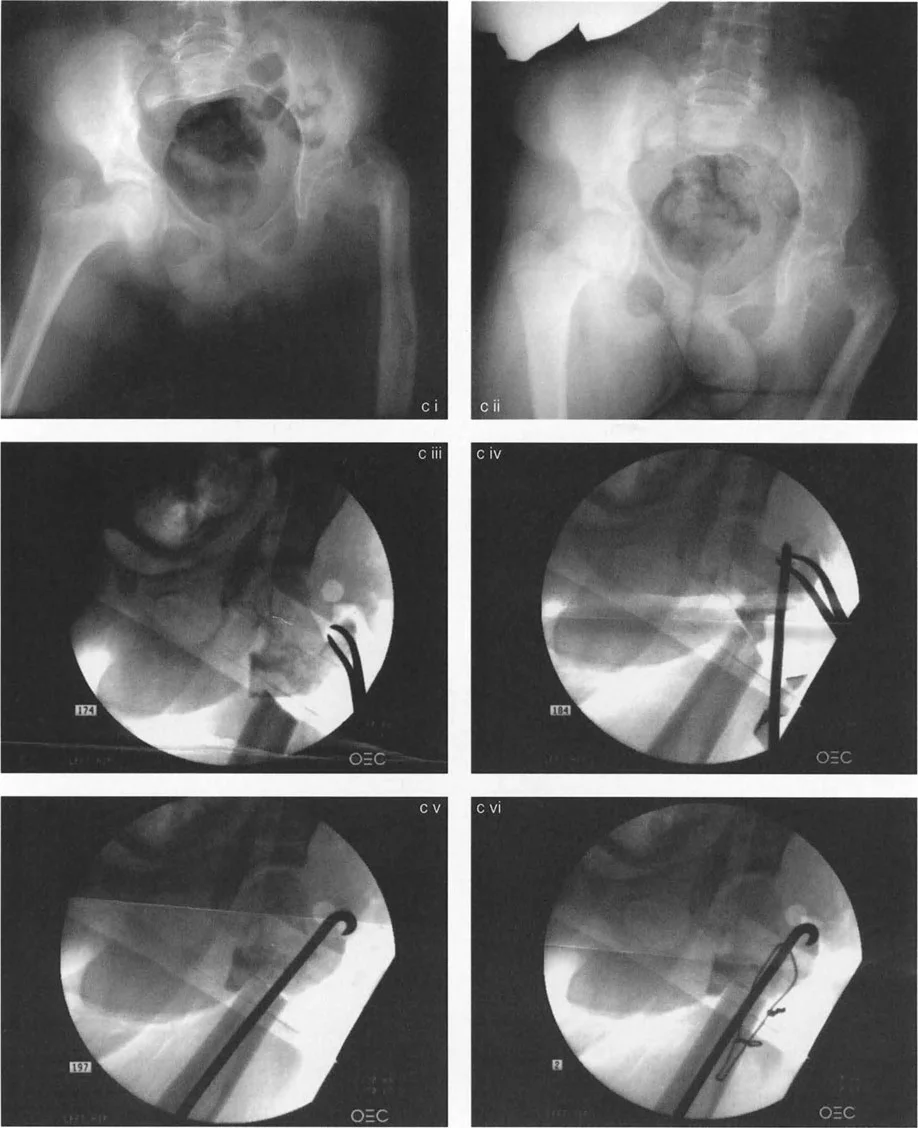

جراحة عظم الفخذ الفحجاء (Valgus Osteotomy) لتصحيح الورك الفحجاء (Varus Deformity)

تُجرى هذه الجراحة عندما يكون عنق الفخذ مائلاً جدًا للأسفل (الورك الفحجاء). تهدف العملية إلى زيادة زاوية عنق الفخذ، مما يجعلها أكثر عمودية.

• التقنية: تتطلب الجراحة قدرة كافية على تقريب رأس الفخذ. في بعض الحالات، قد يكون هناك تقلص في عضلات التبعيد (مثل العضلة الموترة للفافة اللاتسية والعضلة الألوية الوسطى والصغرى)، مما يحد من التقريب.

• إطالة آلية المبعدة: في حالات الورك الفحجاء الخلقي، قد تتطلب إطالة آلية العضلة المبعدة. الأستاذ الدكتور محمد هطيف، في عام 1998، طور إجراءً جديدًا يتضمن إزالة كامل ارتباط العضلة الألوية الوسطى والصغرى بالتواصل مع العضلة رباعية الرؤوس (العضلة المتسعة الوحشية). هذا الإجراء يحرر المدور الكبير من تقلص التبعيد خارج المفصل، مما يسمح بتقريب عظم الفخذ القريب ضمن قيود الارتباطات الكبسولية. كما يتطلب تحرير العضلة الكمثرية التي يمكن أن تحد من الدوران الداخلي والمد والتقريب. يتم إعادة تثبيت الوتر المشترك لهذه الوحدة إلى المدور الكبير بعد تقريب الورك لتصحيح تشوه الورك الفحجاء.

جراحة عظم الفخذ الروحاء (Varus Osteotomy) لتصحيح الورك الروحاء (Valgus Deformity)

تُجرى هذه الجراحة عندما يكون عنق الفخذ مائلاً جدًا للأعلى (الورك الروحاء). تهدف العملية إلى تقليل زاوية عنق الفخذ، مما يجعلها أكثر أفقية.

اعتبارات تحديد مستوى قطع العظم

يعد اختيار مستوى قطع العظم (Osteotomy Level) أمرًا حاسمًا ويؤثر على جوانب عديدة، بما في ذلك توتر وتر العضلة القطنية الحرقفية (Psoas Tendon) ومسافة القطع عن مركز دوران الزاوية (CORA).

• مستويات القطع: يمكن أن يكون القطع فوق المدور الصغير (Intertrochanteric) أو تحته (Subtrochanteric).

• جراحة عظم الفخذ الفحجاء: إذا كان القطع تحت المدور الصغير، فإنه يميل إلى إرخاء وتر العضلة القطنية الحرقفية، مما يسهل التصحيح. إذا كان القطع فوق المدور الصغير، فإنه يشد الوتر، مما قد يجعل الجراحة أكثر صعوبة.

• جراحة عظم الفخذ الروحاء: إذا كان القطع فوق المدور الصغير، فإنه يميل إلى إرخاء الوتر. إذا كان القطع تحت المدور الصغير، فإنه يشد الوتر، مما يزيد من صعوبة الإجراء.

• لذلك، يفضل الأستاذ الدكتور محمد هطيف إجراء جراحة عظم الفخذ الروحاء فوق المدور الصغير، وجراحة عظم الفخذ الفحجاء تحت المدور الصغير، لتحسين النتائج وتسهيل الجراحة.